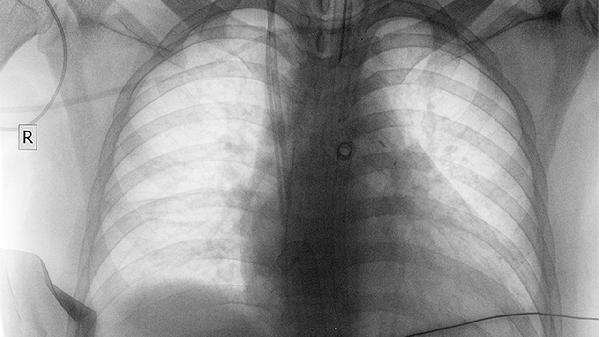

CT检查是诊断肺癌的重要手段之一,但不能单独确诊肺癌,确诊需结合病理活检、支气管镜等检查。 1、影像学筛查 CT...